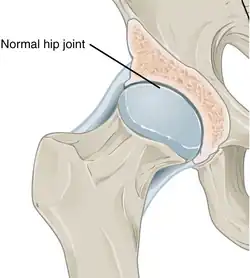

In a healthy joint, the ends of bones are encased in smooth cartilage. Together, they are protected by a joint capsule lined with a synovial membrane that produces synovial fluid. The capsule and fluid protect the cartilage, muscles, and connective tissues. -

With osteoarthritis, the cartilage becomes worn away. Spurs grow out from the edge of the bone, and synovial fluid increases. Altogether, the joint feels stiff and sore. -